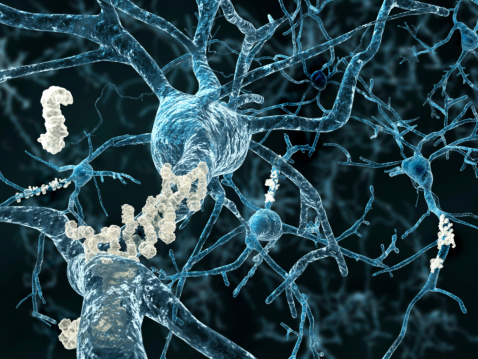

You’re often advised to lower your cholesterol levels because it can result in a heart-related complication. But studies have revealed that having high cholesterol may contribute to a higher Alzheimer’s disease risk. The findings were published in Nature Chemistry and they describe how cholesterol in the brain may act as a trigger for toxic clusters ...click here to read more